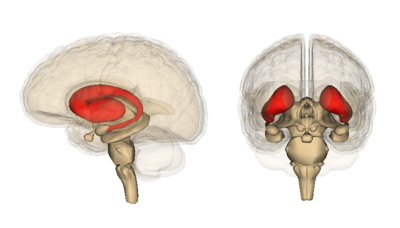

Il volume dell’intero cervello diminuisce più velocemente nelle persone portatrici della mutazione HD, anche se si restringe anche nel corso di un anno nelle persone senza la mutazione HD. Regioni specifiche del cervello che sono note per essere molto sensibili all’HD, chiamate caudato e putamen, sono degenerate ancora più velocemente nelle persone portatrici della mutazione HD. Lo studio ha anche riscontrato perdite precoci della materia bianca del cervello, che è una cosa importante perché è il ‘cablaggio’ del cervello.

Image credit: Life Science Databases

Analisi della potenza e futuro

Delle dozzine di misurazioni per ogni paziente TRACK-HD, la perdita di tessuto nella regione del caudato del cervello è stato il cambiamento più chiaro osservato. Questa perdita di tessuto è stata costantemente più alta in ogni gruppo di portatori della mutazione HD osservati, anche quelli anni prima dei previsti sintomi motori dell’HD. Queste informazioni consentono agli scienziati che conducono questo studio di suggerire che la misurazione del volume di questa regione del cervello potrebbe essere un buon endpoint per una sperimentazione farmacologica nell’HD.